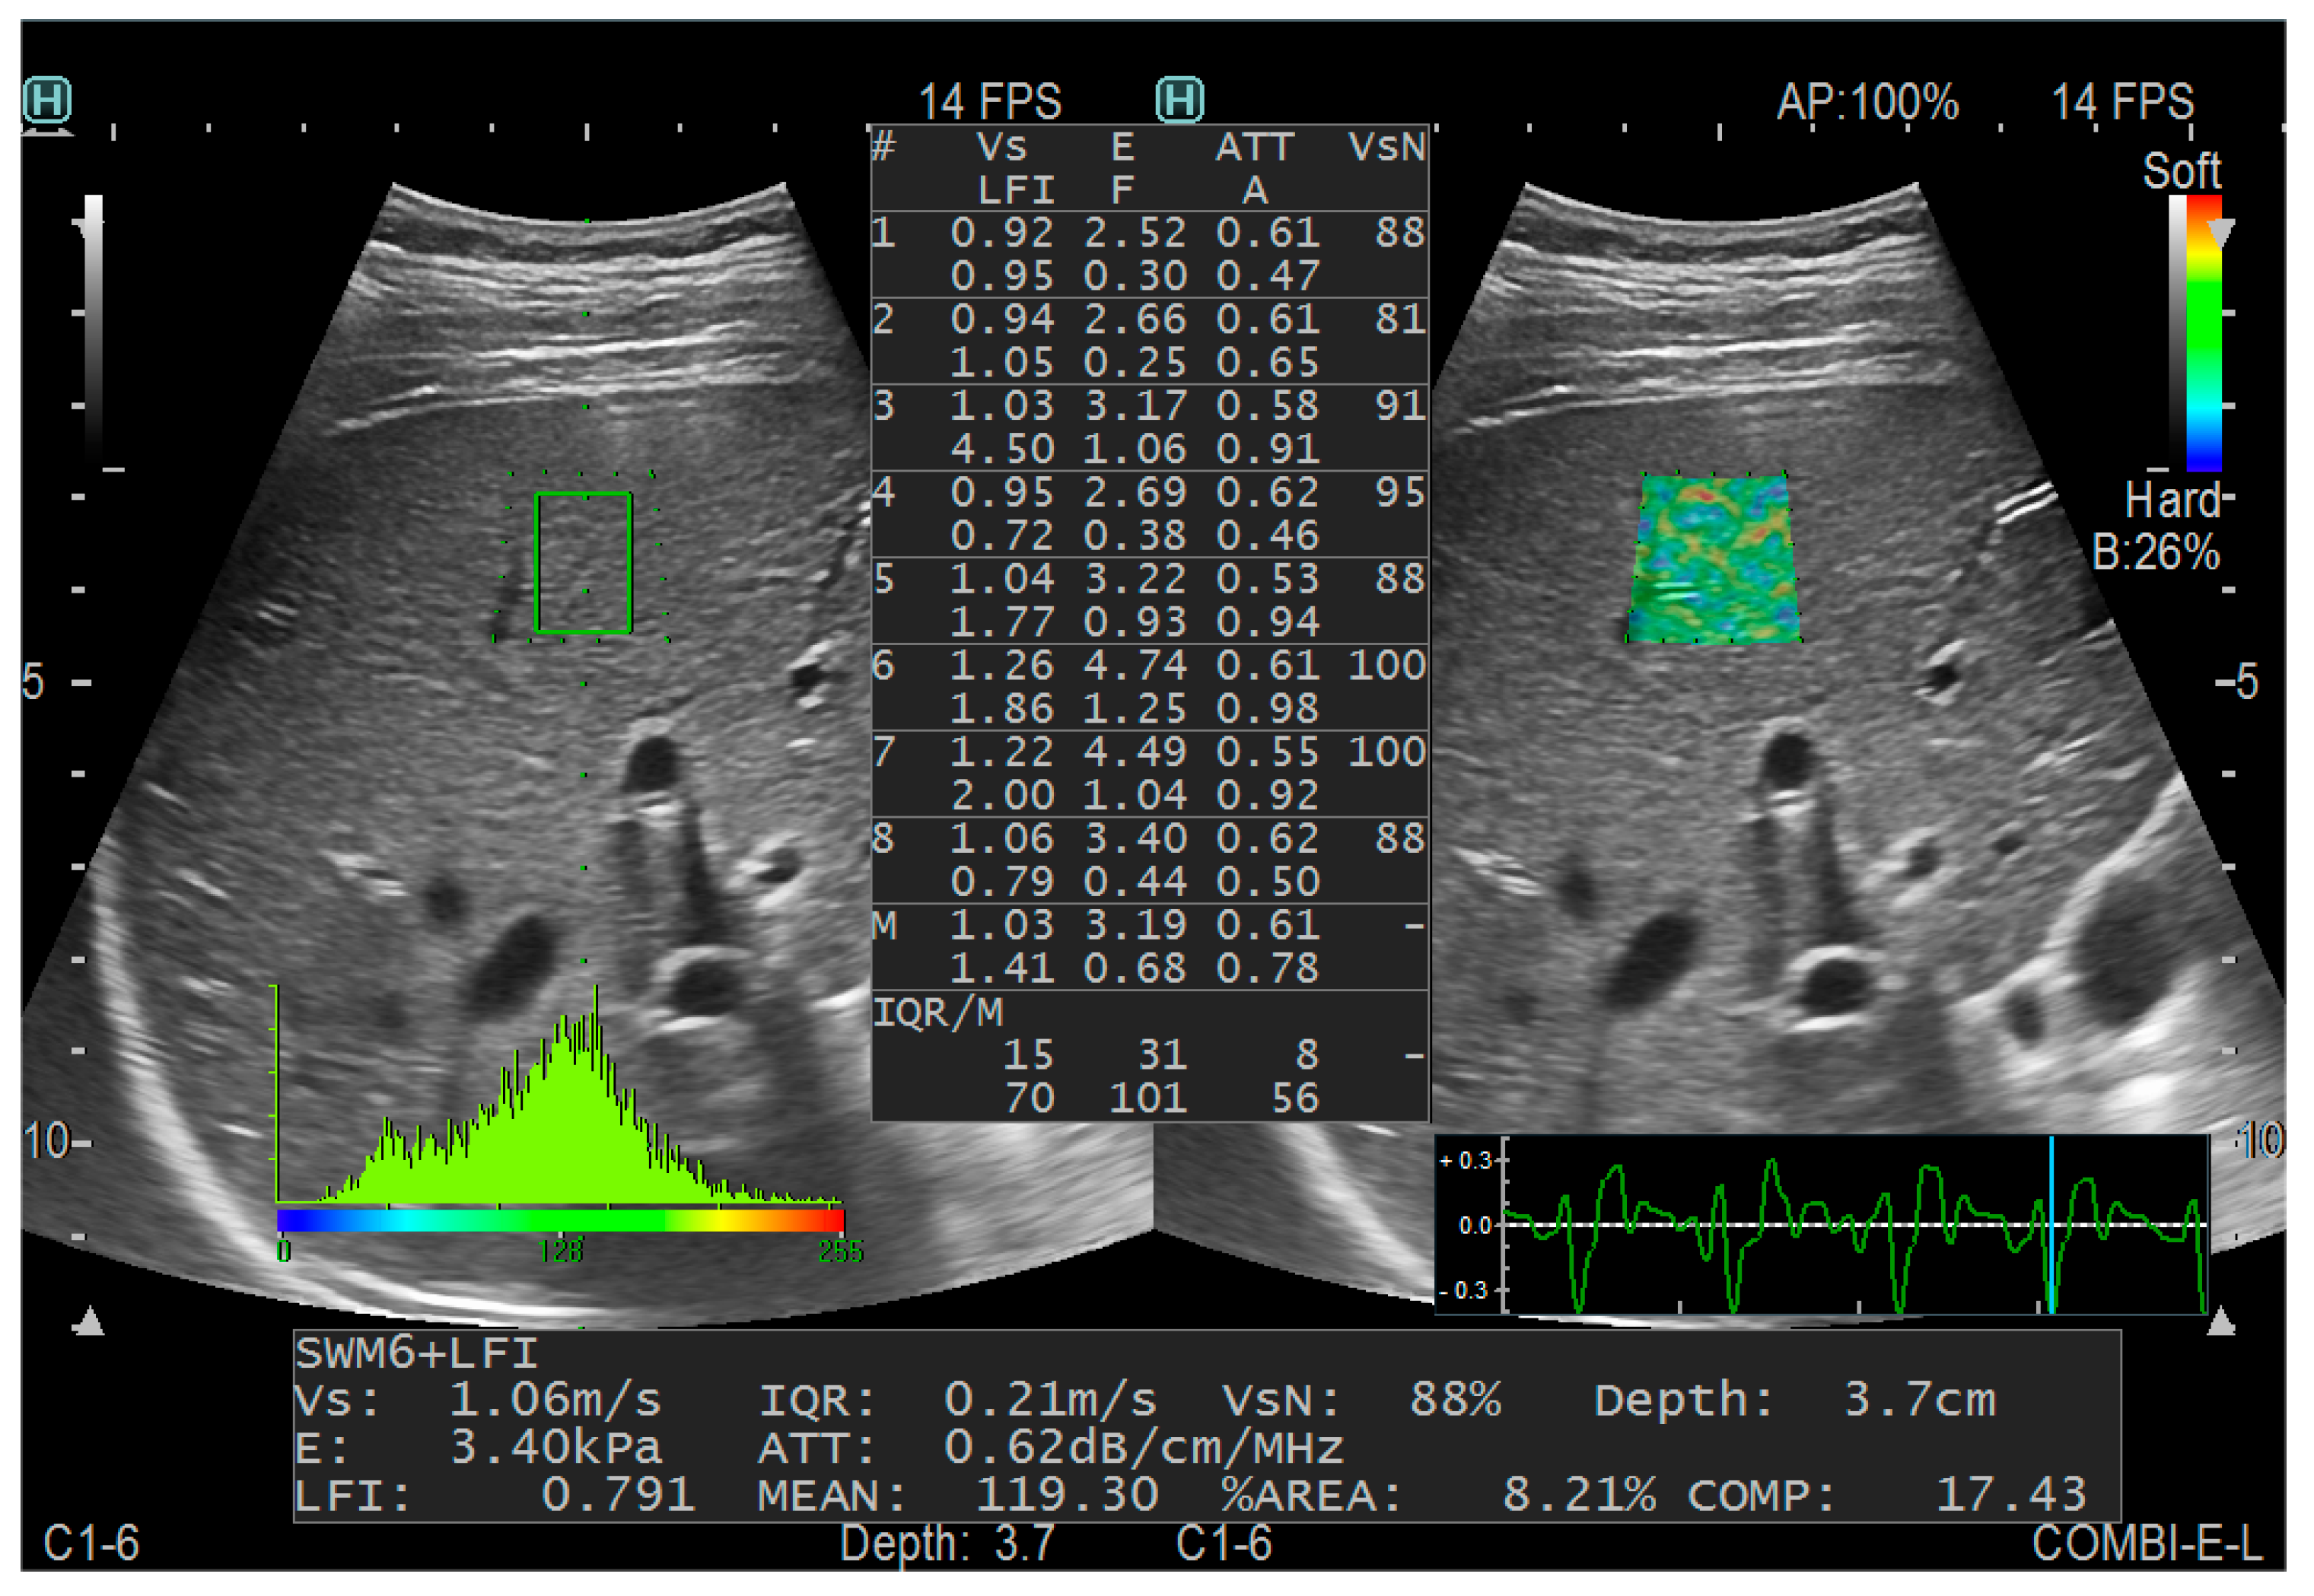

2.2. Imaging Techniques

- Zhao, Y.; Wu, L.; Qin, H.; Li, Q.; Shen, C.; He, Y.; Yang, H. Preoperative combi-elastography for the prediction of early recurrence after curative resection of hepatocellular carcinoma. Clin. Imaging 2021, 79, 173–178. [Google Scholar] [CrossRef] [PubMed]

- Yada, N.; Tamaki, N.; Koizumi, Y.; Hirooka, M.; Nakashima, O.; Hiasa, Y.; Izumi, N.; Kudo, M. Diagnosis of Fibrosis and Activity by a Combined Use of Strain and Shear Wave Imaging in Patients with Liver Disease. Dig. Dis. 2017, 35, 515–520. [Google Scholar] [CrossRef]

- Yada, N.; Sakurai, T.; Minami, T.; Arizumi, T.; Takita, M.; Hagiwara, S.; Ida, H.; Ueshima, K.; Nishida, N.; Kudo, M. Influence of Liver Inflammation on Liver Stiffness Measurement in Patients with Autoimmune Hepatitis Evaluation by Combinational Elastography. Oncology 2017, 92 (Suppl. S1), 10–15. [Google Scholar] [CrossRef]